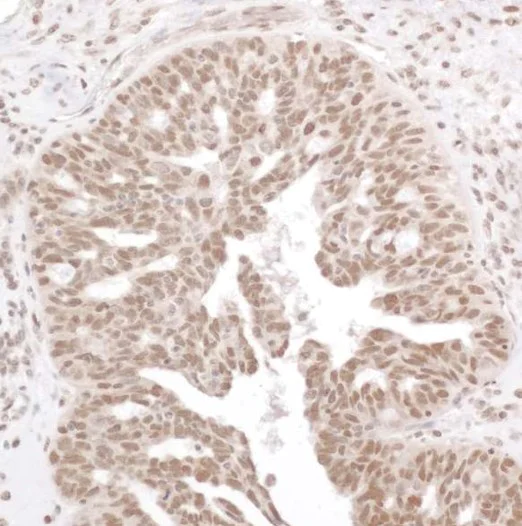

Immunohistochemistry (Formalin/PFA-fixed paraffin-embedded sections) - Anti-NF-kB p65 (phospho S536) antibody (AB86299)

IHC image of NF-kB p65 (phospho S536) staining in Human ovarian carcinoma formalin fixed paraffin embedded tissue section, performed on a Leica BondTM system using the standard protocol F. The section was pre-treated using heat mediated antigen retrieval with sodium citrate buffer (pH6, epitope retrieval solution 1) for 20 mins. The section was then incubated with ab86299, 1μg/ml, for 15 mins at room temperature and detected using an HRP conjugated compact polymer system. DAB was used as the chromogen. The section was then counterstained with haematoxylin and mounted with DPX.